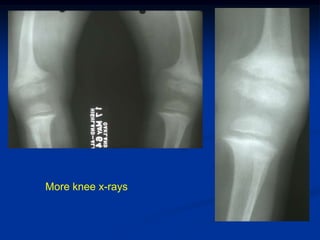

Case #1                     Vit D deficient rickets

One year old with bowing of the lower extremities

More knee x-rays